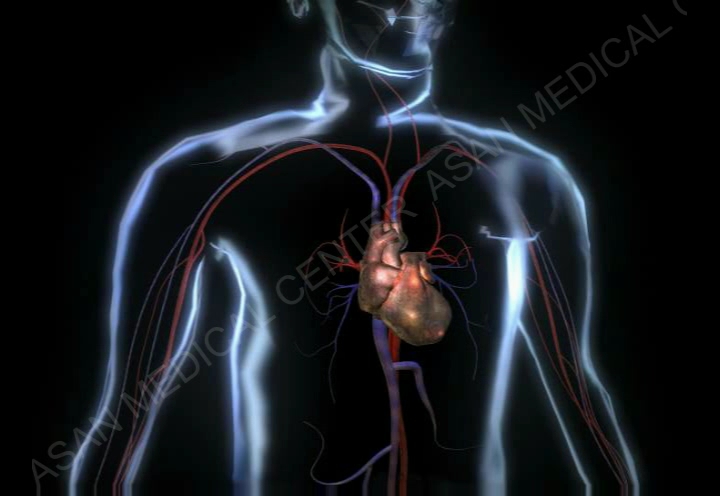

심내막염(Endocarditis)

류마티스 관절염

선천성 심장 질환

심낭 삼출

심장 판막 질환

울혈성 심부전

흉부 대동맥류

복부 대동맥류